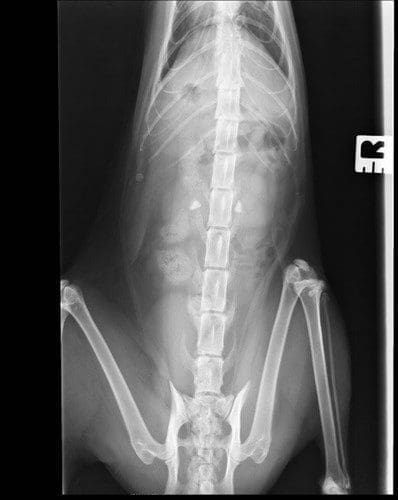

Lateral and DV abdominal radiographs were obtained which confirmed that Lucy has fairly sizeable bilateral renoliths (Figure 2). It would seem likely that these are calcium oxalate given previous history and presence of hypercalcaemia. A Bates body which is thought to occur due to fat necrosis was also noted incidentally.

Figure 2. A right lateral abdominal radiograph. Radiopaque renoliths are visible within the collecting system of both kidneys (red arrows). The incidental fat necrosis appears as a round radiopaque area within the ventral abdomen (yellow arrow).